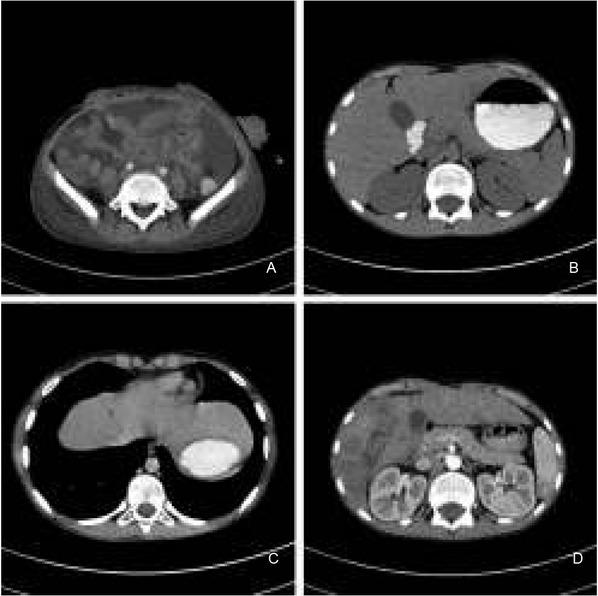

In the anatomopathological differential diagnosis, the following entities were included: alveolar rhabdomyosarcoma, Ewing’s sarcoma/primitive neuroectodermal tumor, GIST, and synovial sarcoma. The definite pathological diagnosis was specified as: clear cell sarcoma-like tumor of the gastrointestinal tract (CCSL-GT), finally designated with its most recent and updated nomenclature: Malignant Gastrointestinal Neuroectodermal Tumor. This diagnosis was additionally confirmed at molecular level. Namely, the EWSR1 Break Apart FISH Probe detected chromosomal breakage at 22q12. A postoperative computed tomography (CT) scan revealed complete atelectasis in the inferior segments of the left lung, hydrothorax, and the persistence of free fluid retention around the urinary bladder and in both iliac fossae. To the right of the aortic bifurcation, another irregular fluid-filled space (33.0x28.0x35.0 mm) was found and interpreted as packages of mesenteric lymph nodes with substantial dissolution of their structures (Fig. 4A). Abdominal tomography shortly after the first surgery revealed there were no detectable metastatic foci in the liver (Fig. 4B). On postoperative Day 11, a second surgery was done: the mesenteric polycyclical mass was surgically removed, the intestine reunited with end-to-end anastomosis, and omentectomy performed. Among the 11 examined lymph nodes from the polycyclical mass, there were 4 nodal metastazes, with the largest metastatic lesion 1.7-cm in diameter and containing a 0.9-cm focus of necrosis. The patient was given CWS 2006 VAIA III chemotherapy (vincristine, adriamycin (doxorubicin), afosfamide, dactinomycin), and later CEVAIE (carboplatin, epirubicin, vincristine, actinomycin D, ifosfamide and etoposide). However, 8 weeks from the first laparotomy, repeated CT and magnetic resonance imaging (MRI) showed 8-16 mm, large metastases to several liver segments (Fig. 4C and D). At 6 months from diagnosis, these lesions were biopsied and histopathologically confirmed to be of metastatic nature. Consequently, thermal ablation of the detected lesions was the next procedure. During the third laparotomy, a mesenteric tumor mass and a tumor bordering both the right kidney and liver were removed. Although CEVAIE chemotherapy was continued, unfortunately, new lesions in the liver emerged. Therefore, etoposide was added to the therapy, yet the patient suffered substantial marrow aplasia after each course of chemotherapy, with fever as a constant symptom. The second thermal ablation of liver foci followed. Due to the progression of liver metastases, pazopanib (a multi tyrosine kinase inhibitor) was introduced. In spite of that, a subsequent abdominal cavity MRI revealed the presence of new hepatic lesions of metastatic appearance. Six weeks later, he was admitted to the hospital for the presence of free abdominal fluid accumulating up to the epigastric region. At that stage, fever up to 39°C, dyspnea related to physical activity, severe anemia, and leukocytosis were present. Escherichia coli was cultured from the aspirated abdominal fluid and broad-spectrum antibiotics were introduced. At 16 months from diagnosis, CT scans demonstrated neoplastic spread outside the liver and enlarged mediastinal and inguinal lymph nodes. Subject to careful palliative care at home, the patient died at 1.5 years of survival from diagnosis.

Further course of the disease as studied with computed tomography. A. Tomographic image of the abdomen after first surgery, large amounts of free fluid present. B. Abdominal tomography shortly after first surgery, no metastatic foci in the liver were detected. C. Abdominal tomography at four months after first surgery, note a small hypodense metastatic liver lesion. D. Computed tomography of the abdomen at a later time, numerous liver metastases.